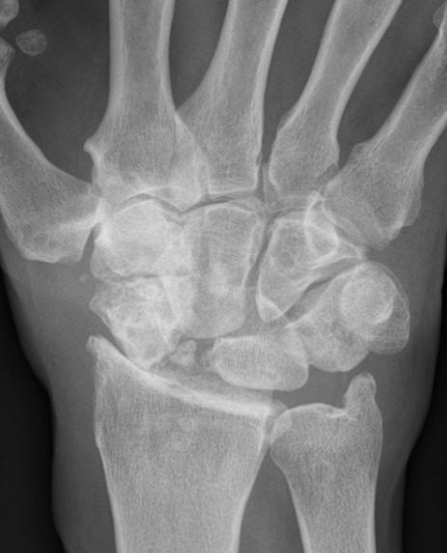

What are seen on xray for a SLAC stage 2 wrist?

PA radiograph

sclerosis

joint space narrowing- between scaphoid and entire scaphoid fossa of distal radius